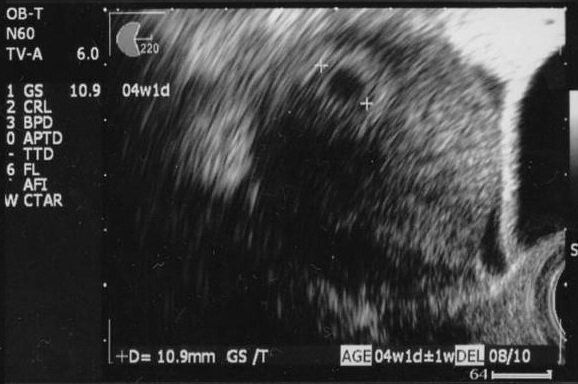

はやしなおさんの妊娠4週目のエコー写真 正常な位置に胎嚢を確認

生理予定日にフライングで妊娠検査薬で検査。結果はうっすら陽性。そこから約1週間の間に2度検査薬で妊娠を確認。待ちに待った2人目妊娠を日に日に確信しました。妊娠4週目で産婦人科へ。胎嚢5.7mmと想像よりだいぶ小さく、まだ安心はできないと自分を落ち着かせたのを思い出します。なるべくいつも通りに生活をしようと心がけました。